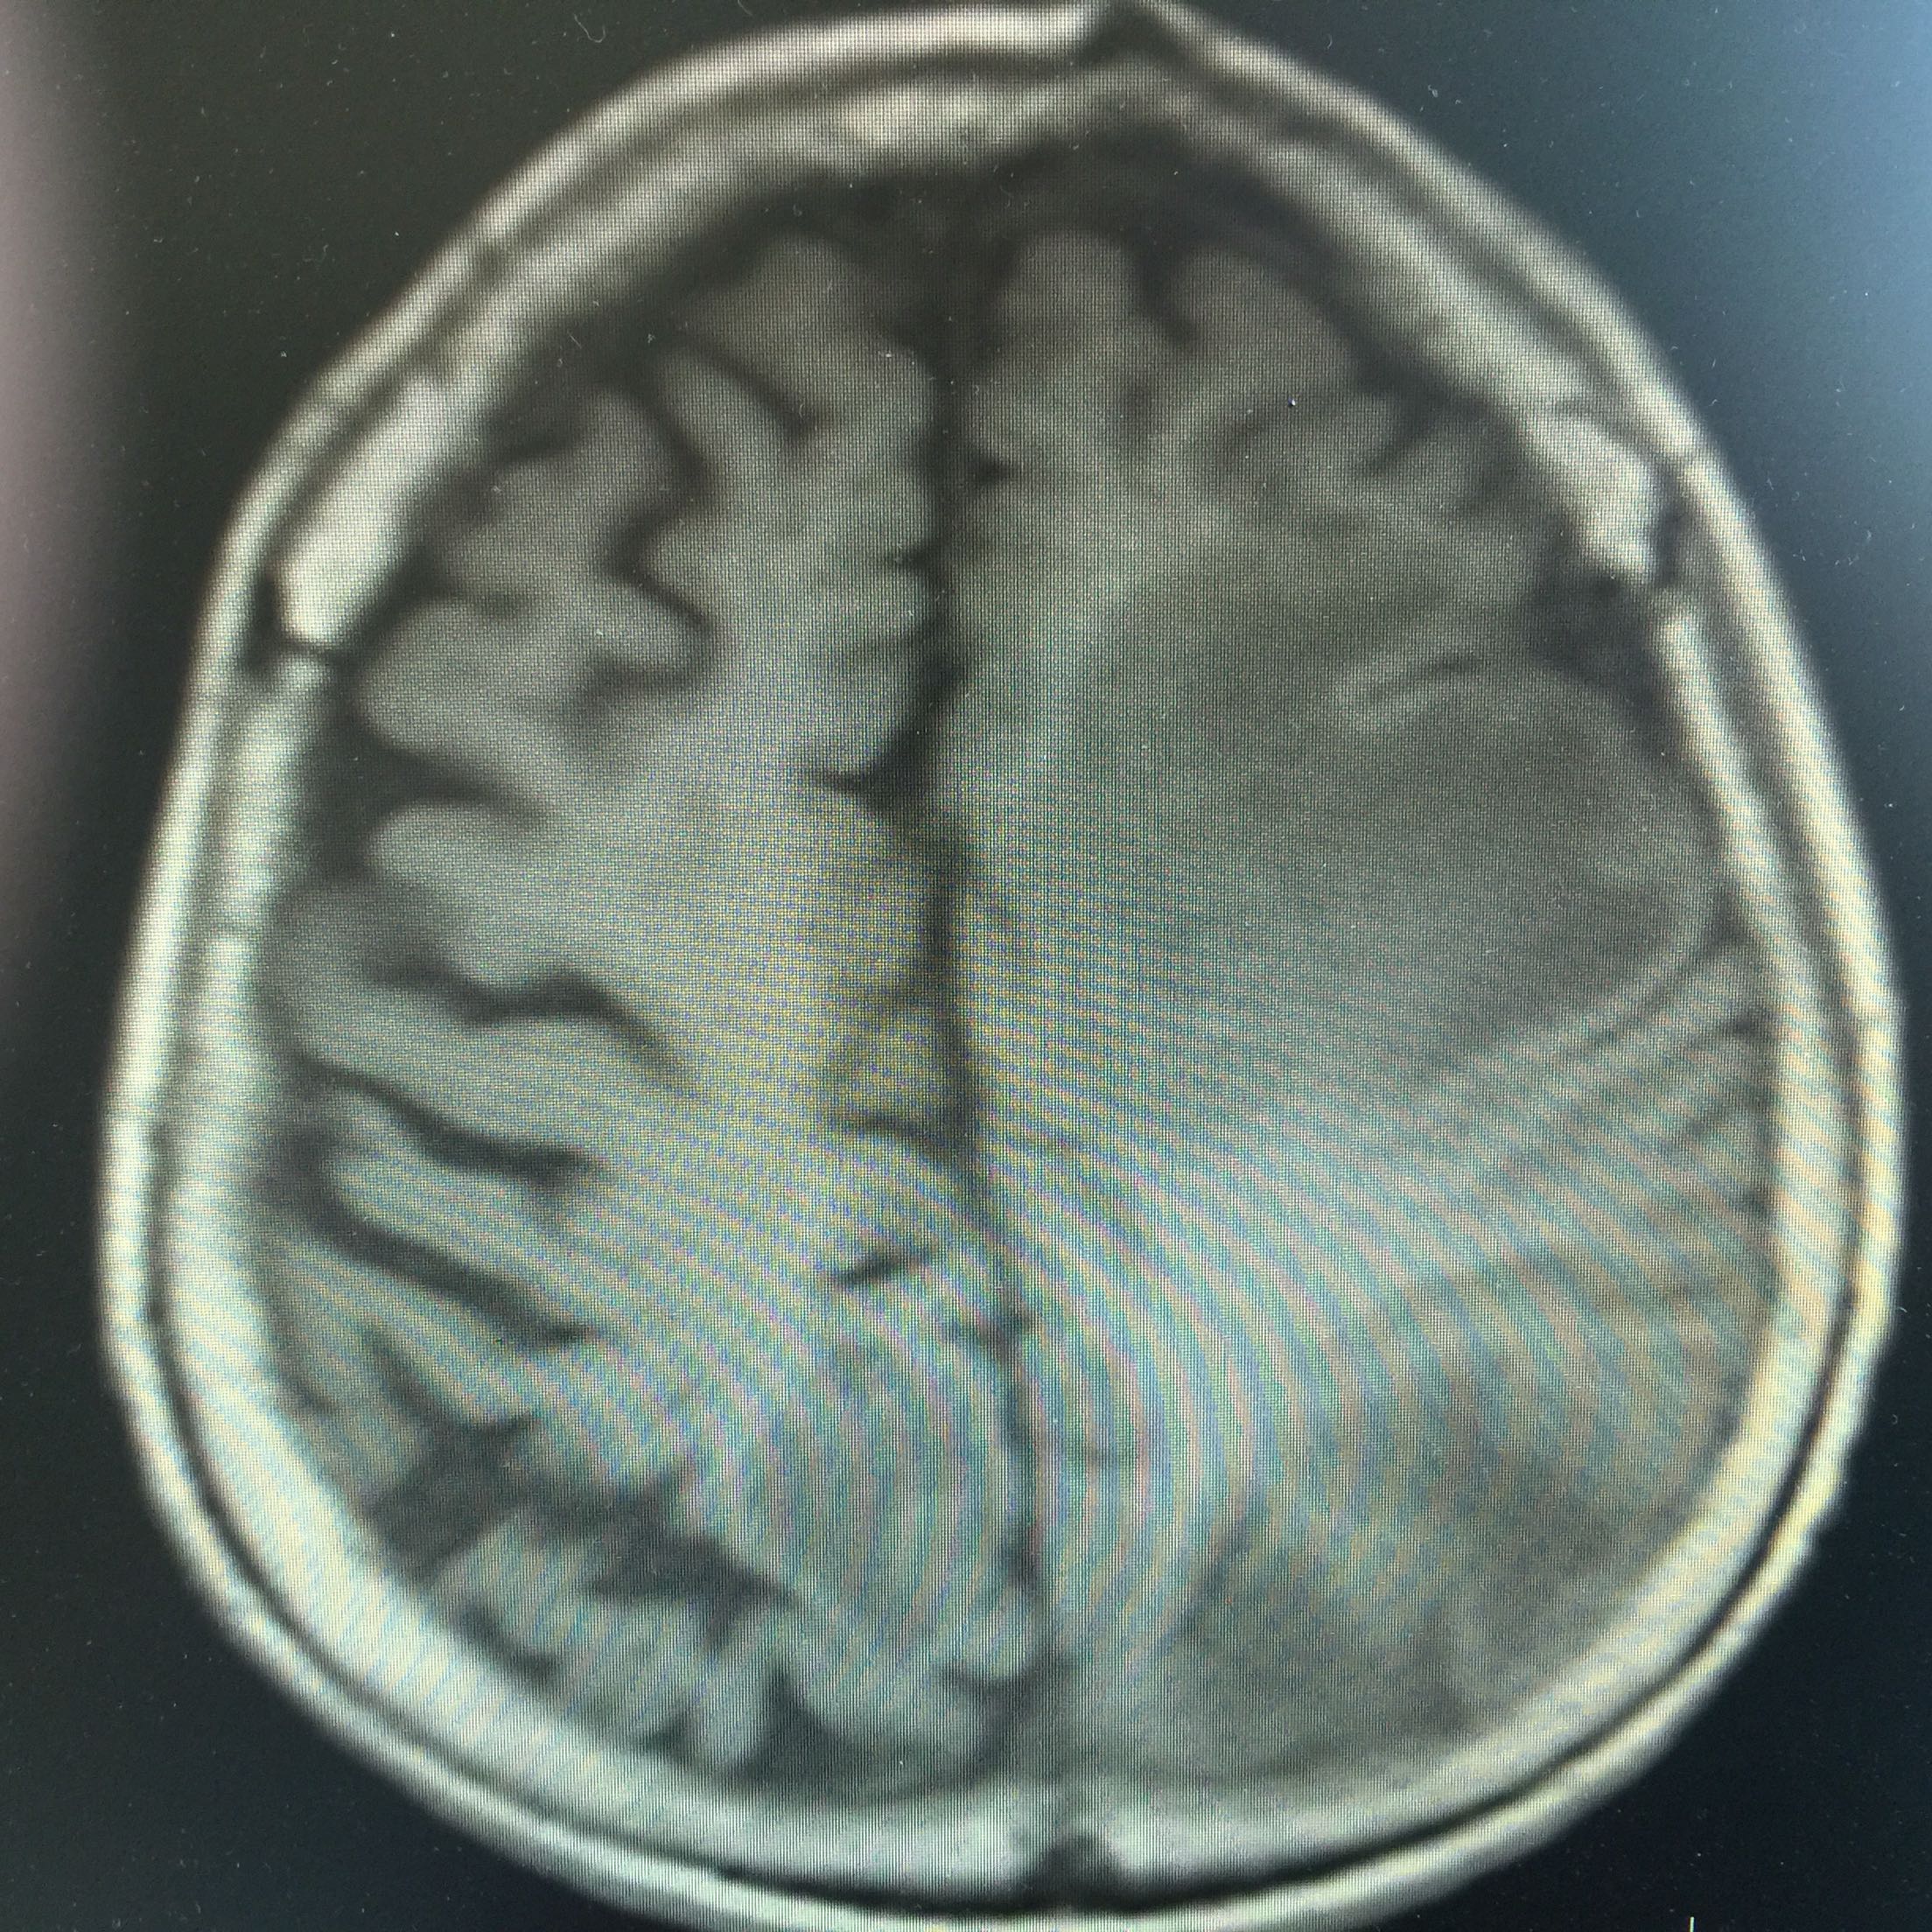

1.女,81岁,以“右侧肢体无力3天”入院。 2.现病史:3天前无诱因出现右侧肢体无力,右上肢抬举费力,右下肢步行拖拉,无抽搐,无意识障碍! 3.既往史:2016年肺穿刺活检,免疫组化为腺癌!已合并第五、六椎体转移、左肾上腺转移,行灌注介入治疗。

左肺腺癌 骨转移、双肺门及纵膈淋巴结转移、左肾上腺转移、脑转移! 治疗:对称、支持治疗!